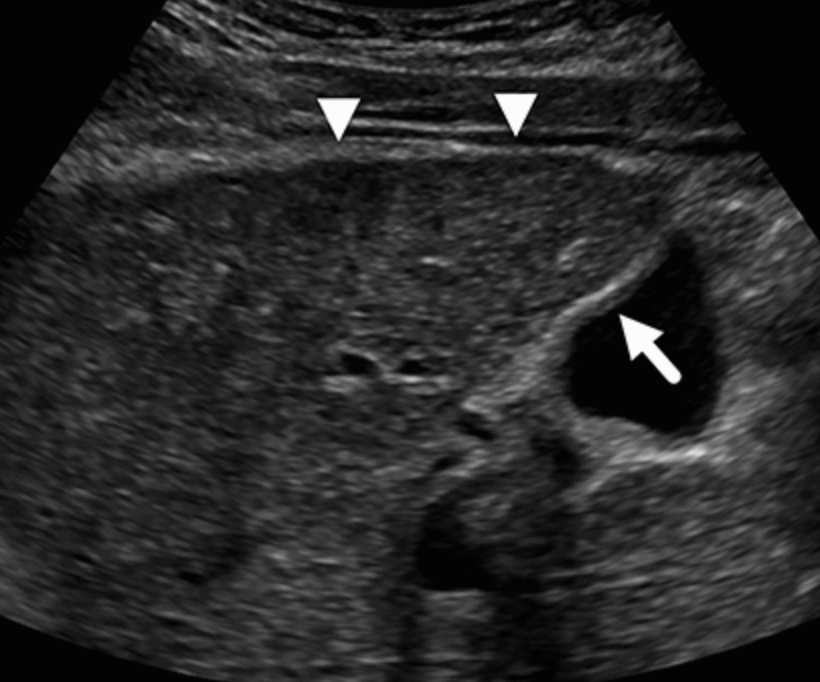

- 담낭이 수축하고 담낭벽이 두꺼워진다.

- 담낭벽(GB wall) 이 3mm 이상 비후된다.